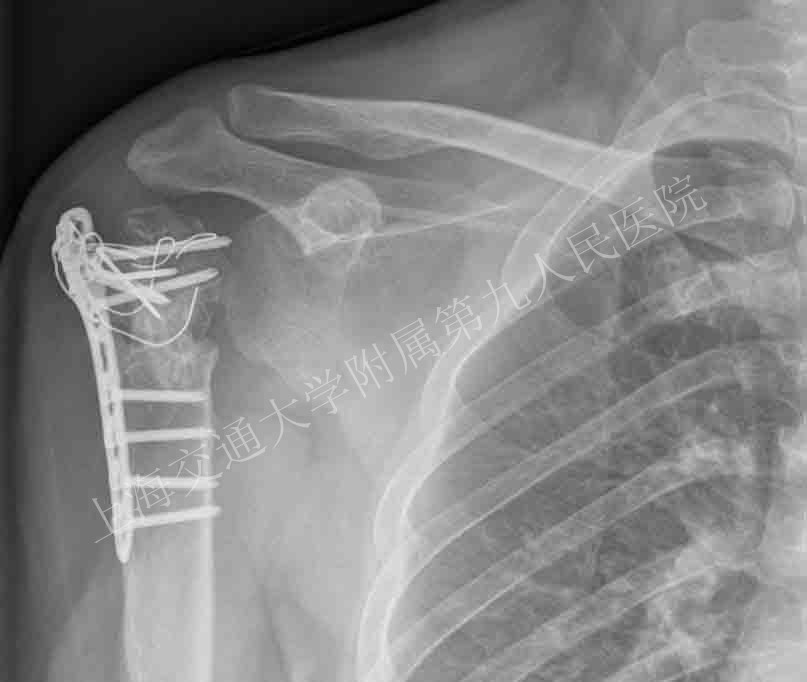

术前照片